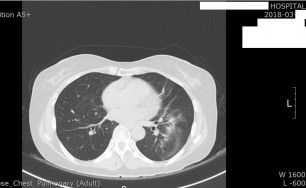

기관지확장증의 CT 사진